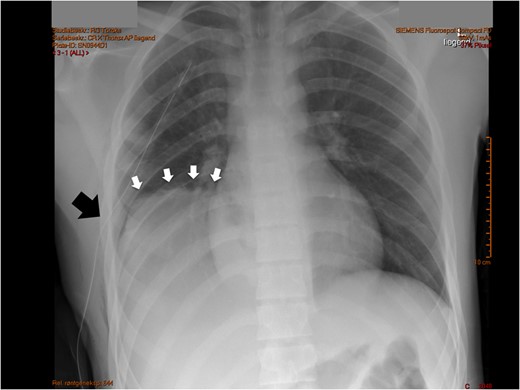

An adolescent male suffered a high-velocity fall while exercising ski-sports in the Alps. He suffered a severe blunt injury with temporary loss of consciousness and was brought to a local hospital where initial work-up and imaging showed no head injury other than a concussion, a right-sided pulmonary contusion with haematothorax and a grade II liver laceration involving segment 8. A right-sided chest drain was placed (Fig. 1) and was kept for several days with strict bed rest and monitoring under conservative management. After 14 days, he eventually was deemed fit for ground-ambulance transfer to our hospital. The chest drain was removed 4 days prior to departure.

Initial chest X-ray after placement of thoracic drain. White arrows note a high-stand of the right diaphragm, black arrow points to chest drain.

On admission after transfer to our hospital he had stable vital signs, with none or little complaints or symptoms. The transferred radiological images from the primary hospital were reviewed and gave immediately suspicion of additional pathology in the right hemithorax, based on a prominent right-sided high-stand of the diaphragm (Fig. 1). A CT scan was made showing a grade II liver laceration and a herniated liver through a large right-sided defect of the right diaphragm (Fig. 2A and B).